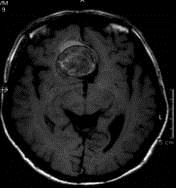

问题 病历摘要:??患者男性,56岁,因右侧视力下降伴视野缺损2个月来院就诊,诉头痛,无明显头晕,无视物重影,无恶心呕吐,无肢体抽搐,无肢体乏力,胃纳佳,大小便正常,既往史无特殊,入院检查:神志清楚,言语清楚,体毛分布正常,左侧视力4.6,右侧视力4.0,粗侧右颞侧视野缺损,左侧正常,颈软,四肢肌张力正常,肌力正常,病理征(-)。 巨型动脉瘤根据瘤腔内血栓的多少如何正确分型?

选项 A.小部分血栓形成 B.大部分血栓形成 C.部分血栓形成 D.不完全血栓形成 E.完全血栓形成 F.无血栓形成

答案 CEF